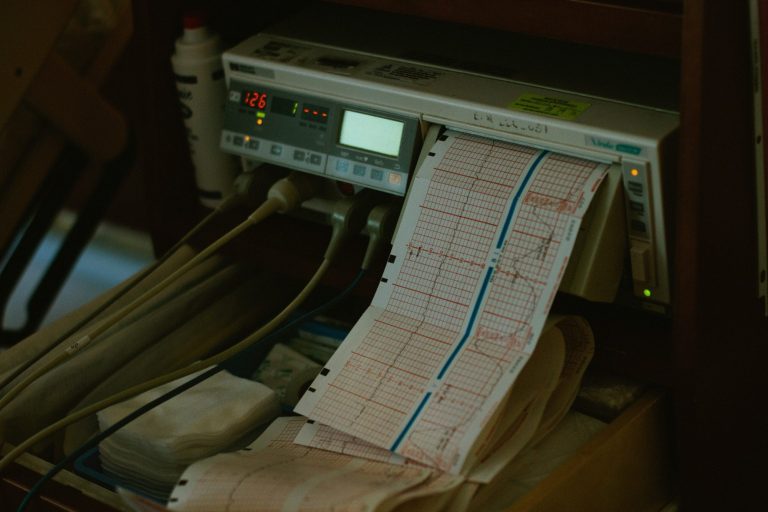

Ergometrie

Belastungs-EKG zur Beurteilung der Herz-Kreislauf-Leistung